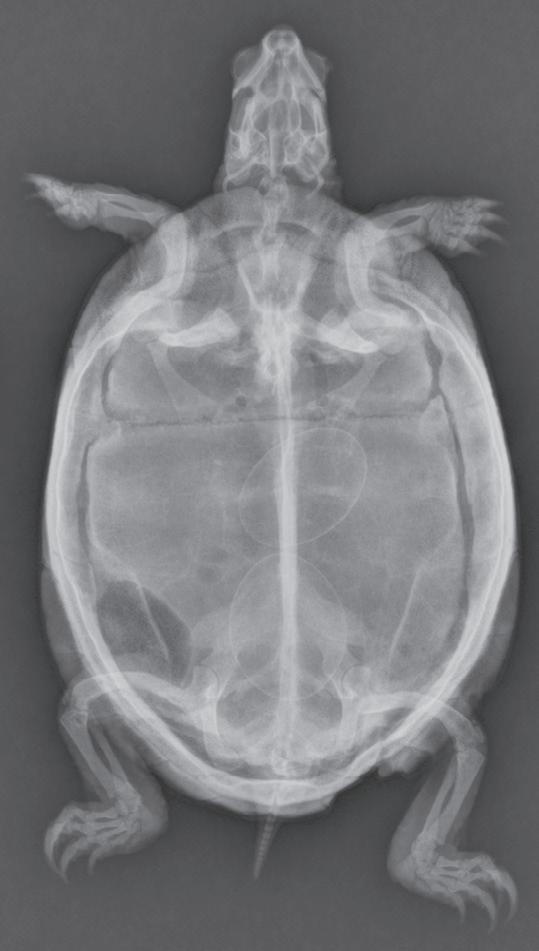

Figure 1-6. Dorsoventral (A), lateral (B), and rostrocaudal (C) radiographs of a box turtle. In A and B, which are orthogonal to each other, it is clear that the subject is a turtle. Eggs are visible in the coelom. In C, which is also an orthogonal view with respect to both A and B, it is not obvious that the subject is a turtle because this orientation is uncommon and unfamiliar. The eggs are also not visible in C.